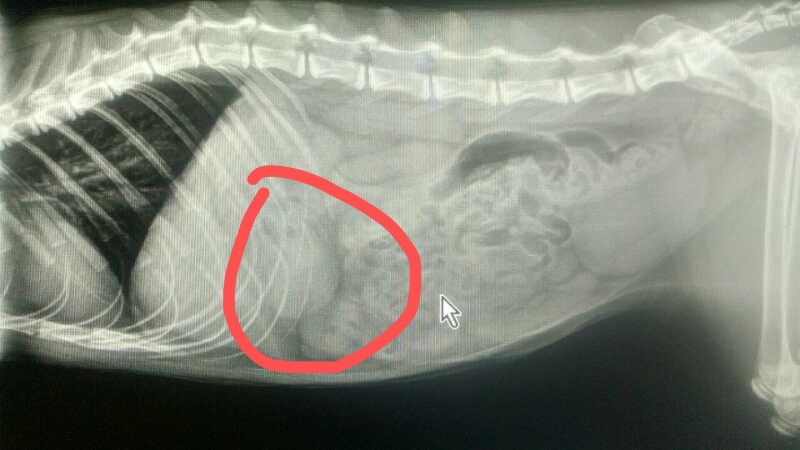

同事家的猫弟弟因为酷爱钻沙发或床底下,结果误食了异物(后来证实是一根逗猫棒掉落的羽毛),不吃不喝,一直吐黄水,去医院一查才发现升级成为了异物胃炎。本来猫咪是可以呕吐或随粑粑拉出来的,可是平时吃到的毛发过多,胃早就承受不住,异物稍微一刺激就引发了炎症。。。也正是这件事情给我们养猫的人再次敲响了警钟:养猫家庭务必要比普通家庭更要注意卫生清扫!尤现在夏季,每天都要开窗通风,再加上主子掉毛季,浮毛和脏东西剧增,猫咪每天滚一滚、舔一舔,不知道吃进去多少脏东西,危险指数大大增加。另外家里如果不注重清洁,毛发、食物碎渣和灰尘等还会滋生细菌,对人宠来说都是患病来源。所以不管多累,都要为了自己和猫,将家里保持干净,整洁。说起清洁打扫一定又有铲屎官极力推荐吸尘器,但是我这种懒癌本癌早就开始瞄上了更省力的工具——扫地机器人。不止打扫更便捷,有时候还能给我当保姆带带猫啥的。![]()